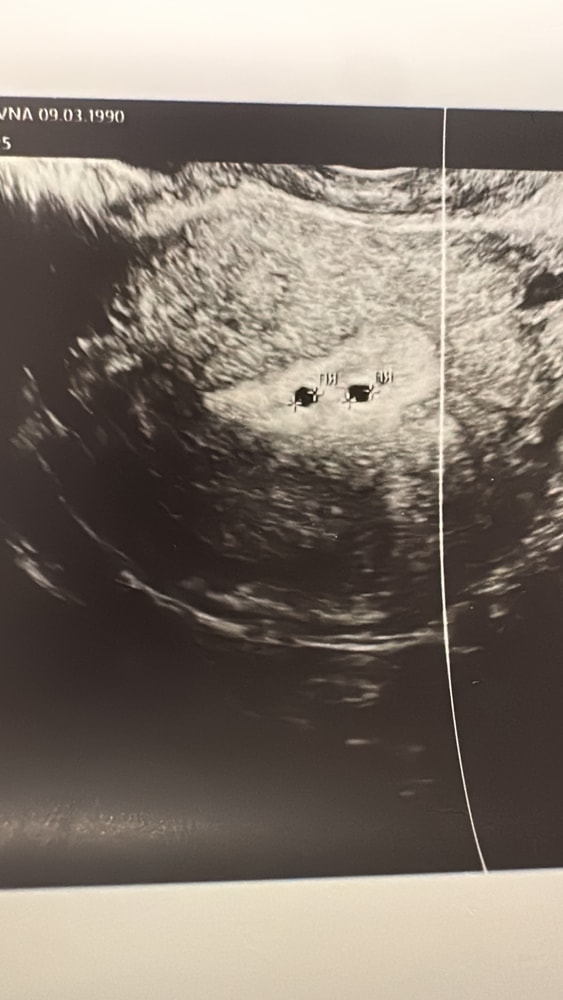

узи на 23 день цикла, 2 желтых тела 21 мм и 22мм, энд 14.

при этом в матке 2!! Анэхогенных включения округлой формы 2,7 мм и 2,6 мм

Вопрос - что за анэхогенное включение, врядли это пя?хгч нет, значит и в матке нет. Узистка очень удивилась,сказала очень похоже на б. врач молчит, говорит ждать. Но как можно увидеть пя на 6 дпо когда даже Хгч нет 😭😭😭 еще ждать неделю хотя бы, мозг кипит.узи делала платно в очень хорошем мед центре. Может кто-то сталкивался с таким ?

Танюшка, я тоже задаюсь вопросом. Ее смутило наличие 2 жт 21 мм и 20 мм. И два одинаковых кружочка в матке. Сказала что киста конечно может быть, но слишком они ровные круглые и почти одинаковые. Так только при беременности бывает. Сказала что кисты такие красивые крайне редко случаются